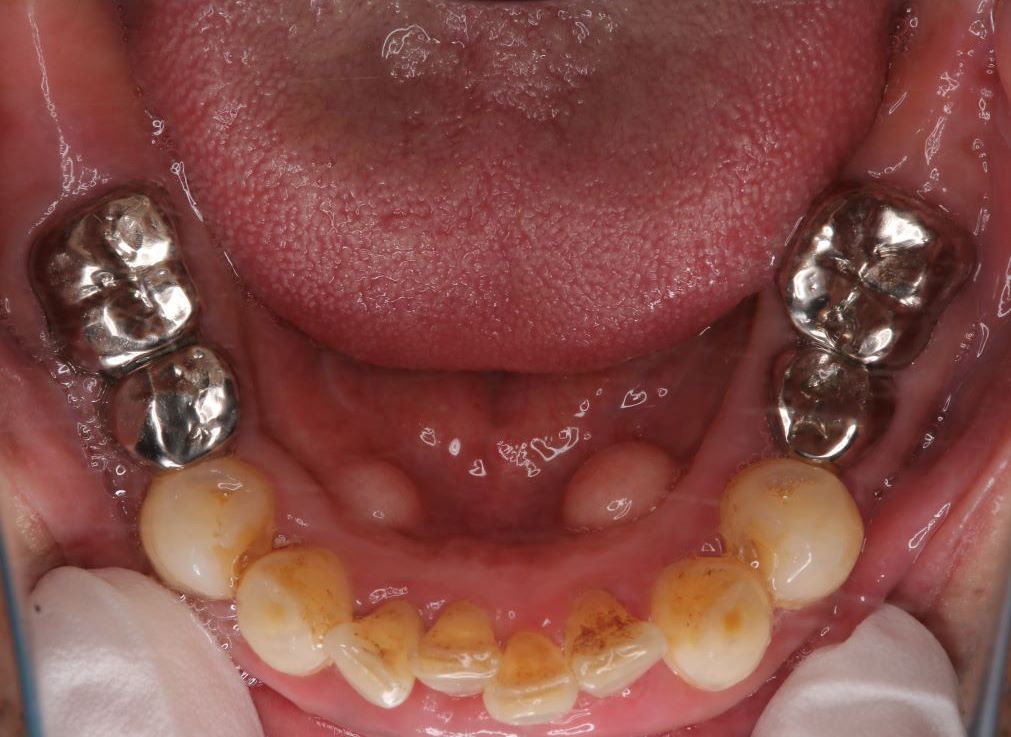

case 02.

BEFORE

AFTER

見た目を重視した治療を希望されている

(リスク)